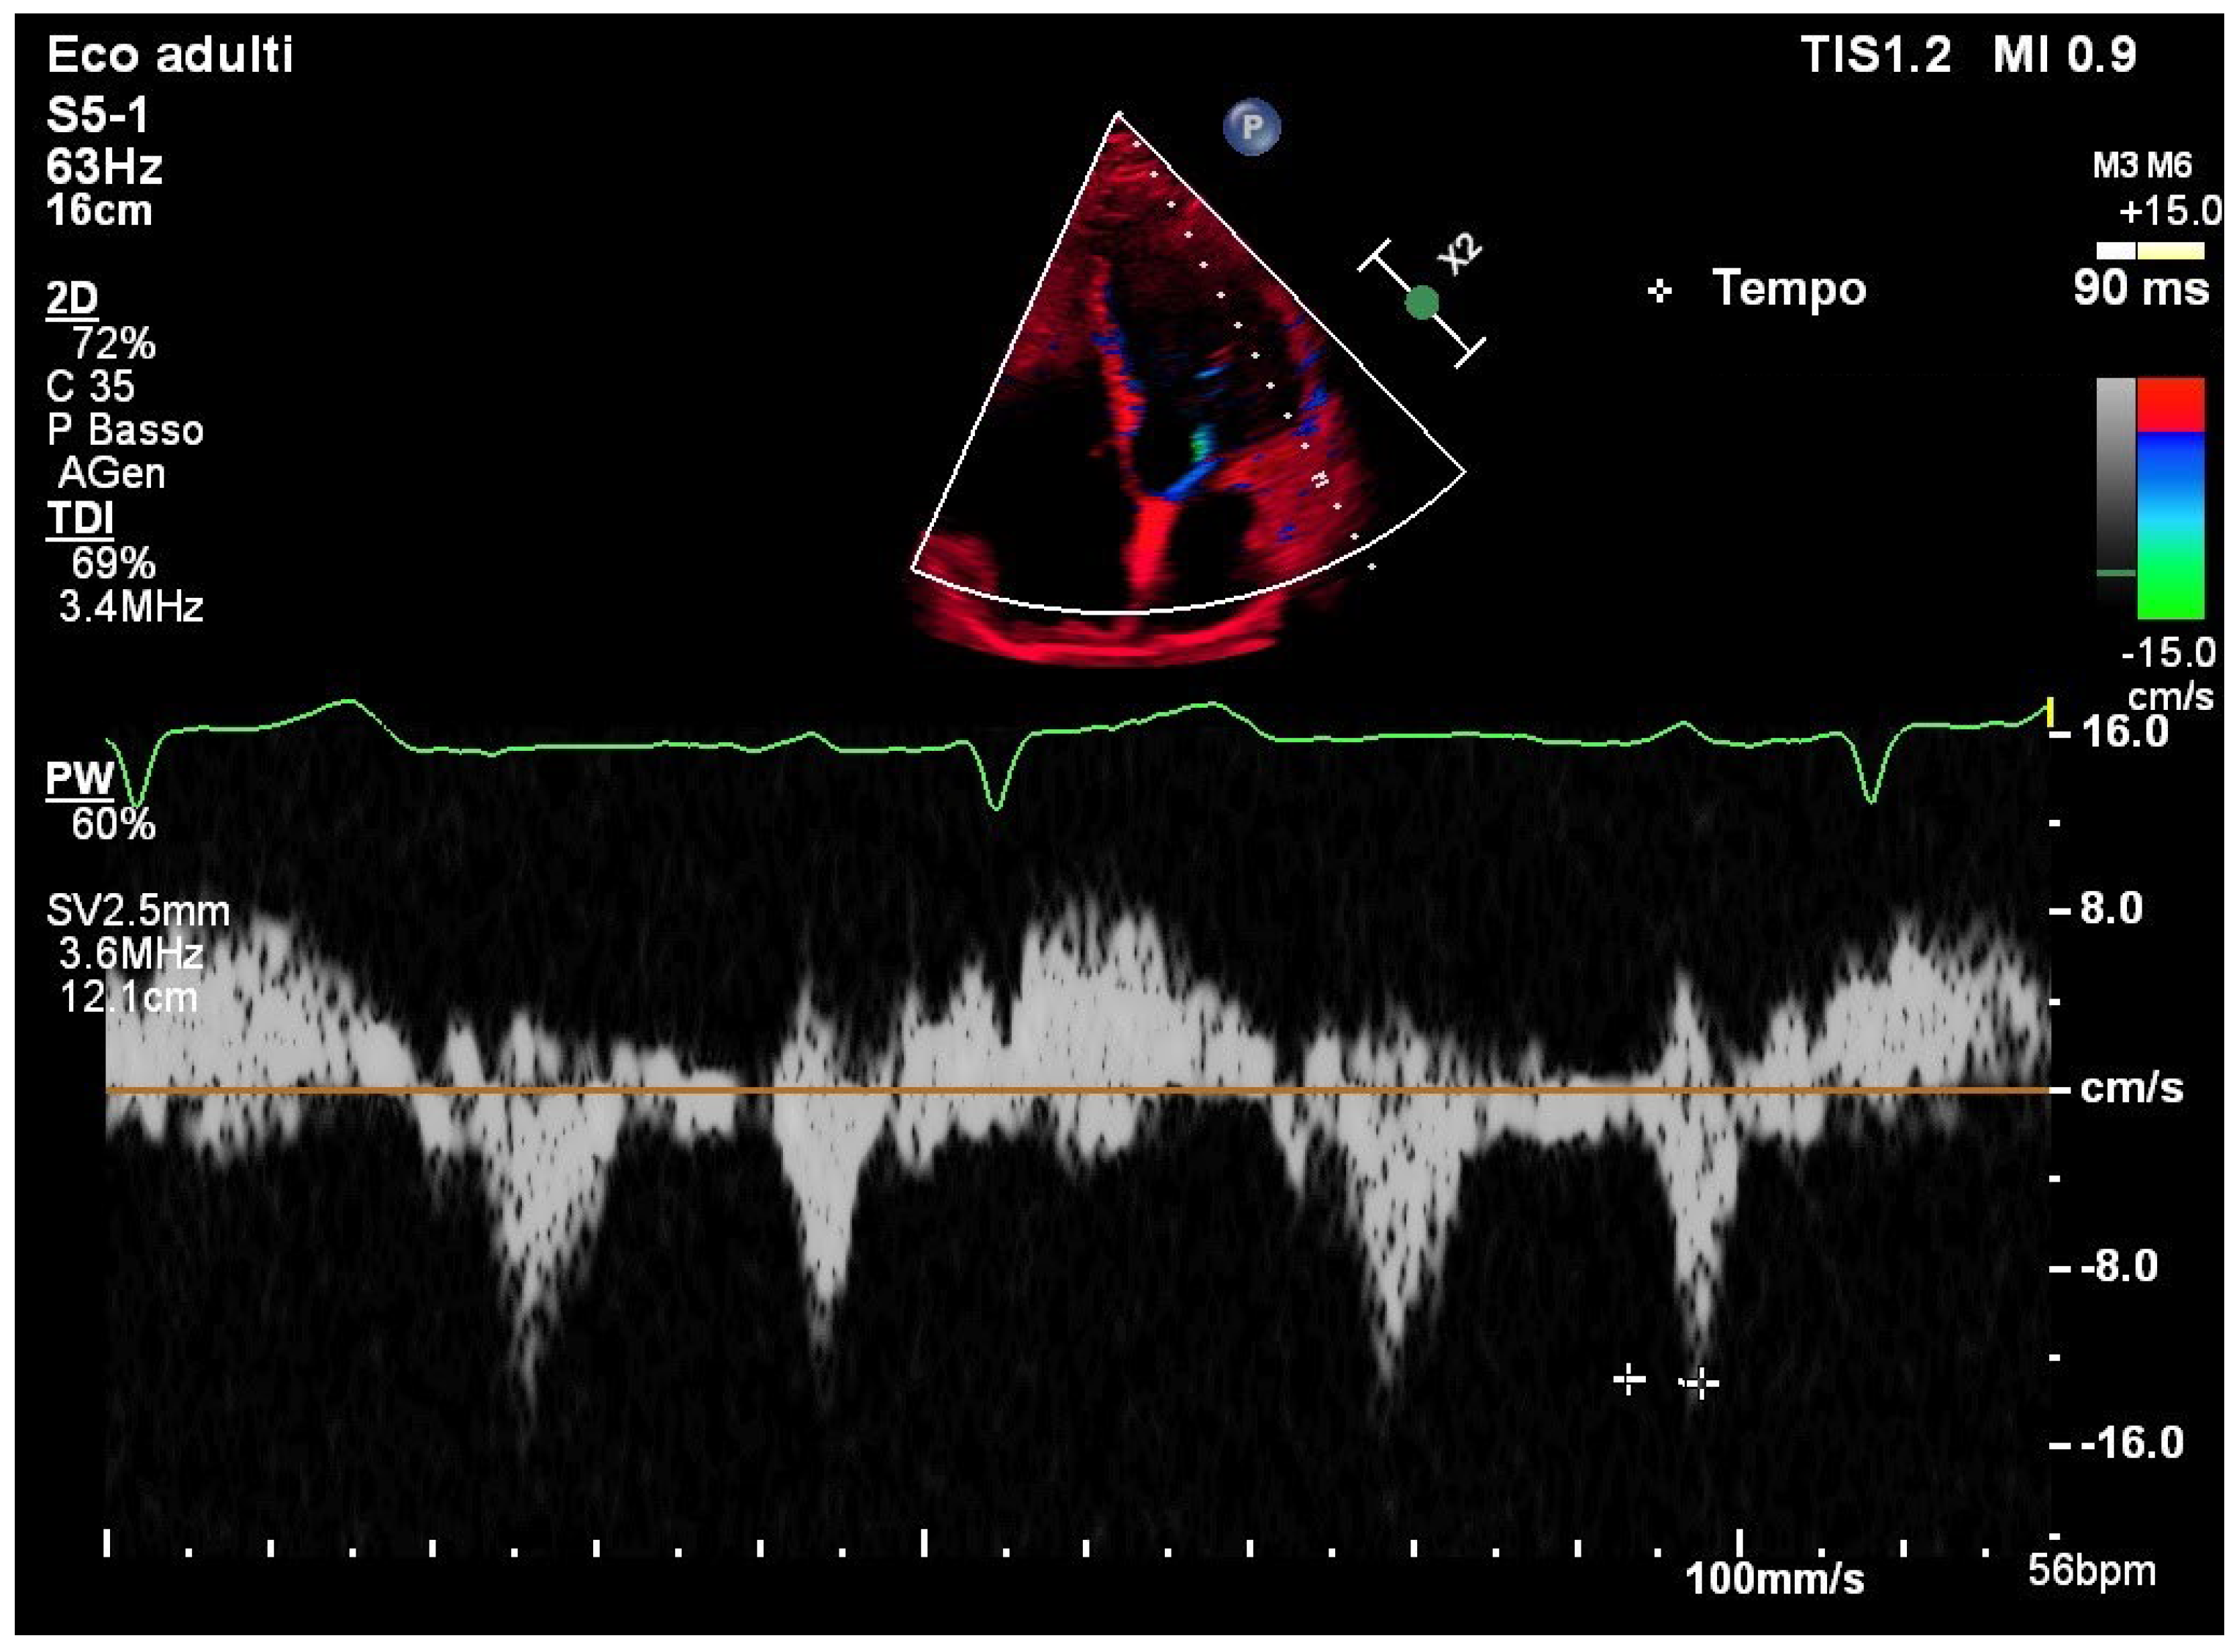

TDI of the lateral mitral annulus showed a normal PA-TDI interval of 90 msec, consistent with preserved intra-atrial conduction (Figure 3).

Figure 3. Tissue Doppler imaging of the lateral mitral annulus showing normal PA-TDI interval.